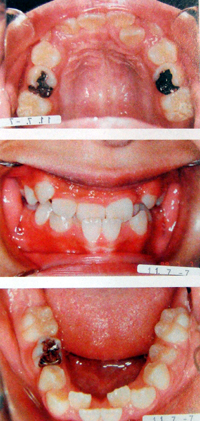

顎(あご)が小さいと、歯がきれいに並びきらないために、歯並びが悪くなりがちです。歯並びが悪いと虫歯や歯周病になりやすくなるだけではなく、いびきや無呼吸症候群になることがあります。

顎を成長させて、口の中の空間を広くし、歯並びも整えます。同時に空間が広がることにより、呼吸がしやすくなり、いびきや睡眠時無呼吸症候群を抑制することができます。

この装置はNHKスペシャル「病の起源」シリーズの睡眠時無呼吸症候群の番組で使われた矯正装置です。放送回では顎の発育が不十分で気道が狭い子供に用いられました。

上記のような例で、症状が出ている場合、抜歯をせず口の中の空間を広くする装置を使用することで、症状をなくすことができます。

子供の場合・1日10時間装着

空間を広げ呼吸を楽にします。